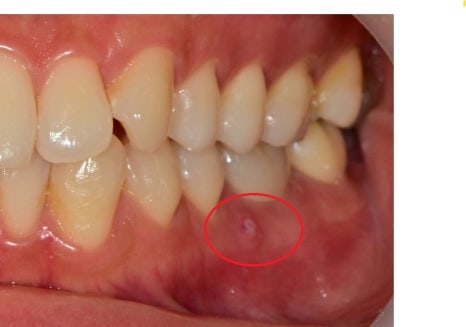

좌측 사진은 잇몸에 고름주머니가 생긴 증상이고,

이것은 뿌리 쪽 염증이 바깥 뼈를 녹이며 외부로

노출이 된 상태이며

이것을 확인하기 위해 고름주머니를 통해

염증의 근원지가 어디인지 엑스레이를 통해 알아보았습니다.